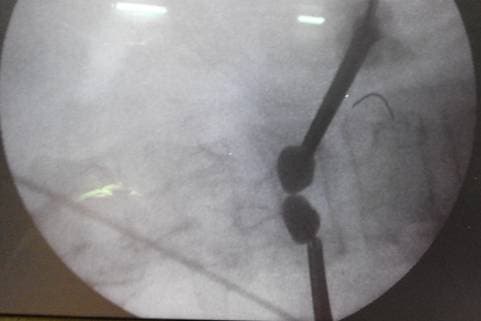

Баллоны в теле позвонка в раскрытом состоянии

Специальные баллоны установлены в теле позвонка и раскрыты для восстановления высоты